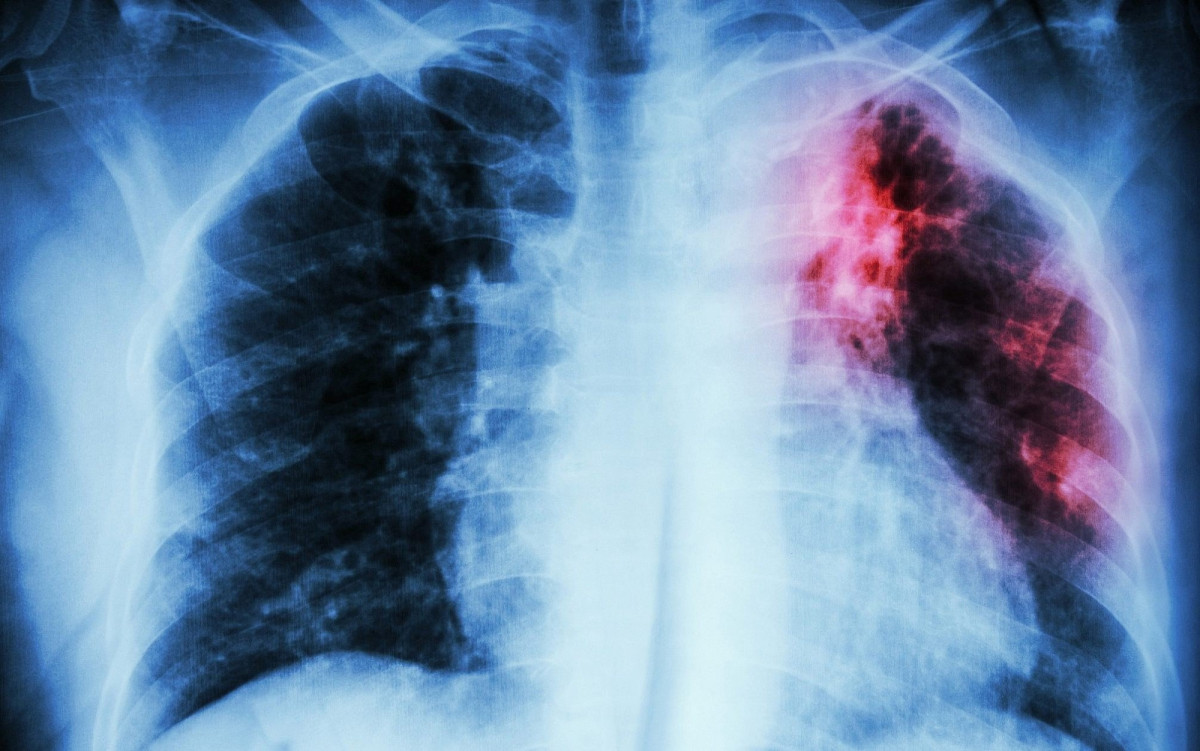

В 2023 году у 1,5 тысячи кузбассовцев обнаружен туберкулёз

За 2023 год туберкулезом в Кузбассе заболели почти 1,5 тысяч человек По данным Роспотребнадзора, за 11 месяцев прошлого года с поставленным диагнозом «туберкулёз» в медучреждения региона попали 1428 человек.

В основном опасным вирусом заболевали взрослые люди. Зафиксированы и случаи, когда инфекцией заразились дети до 14 лет. Их оказалось 43. Почти 25% попали в больницу в возрасте с 15 до 17 лет (статистика составлялась исходя из заболевших, у которых обнаружили поражение легких впервые).

Что касается территорий, где было выявлено больше всего заболевших с начала 2023 года - лидером по заболеваемости стал Кемерово, где зафиксировали 318 случаев. На вторую строчку попал Новокузнецк с 245 заболевшими. Закрыл тройку антилидеров Прокопьевск, где выявили 96 случаев заражения.